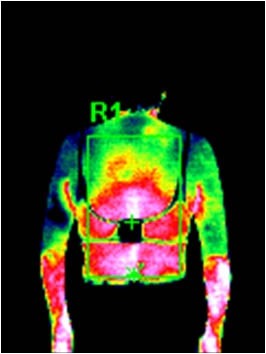

サーモグラフィによる水素水風呂入浴後の実験データです。

普通入浴 15分入浴後

| R1 | 平均温度 | 34.1℃ |

| R1 | 最高温度 | 36.2℃ |

| R1 | 最低温度 | 28.8℃ |